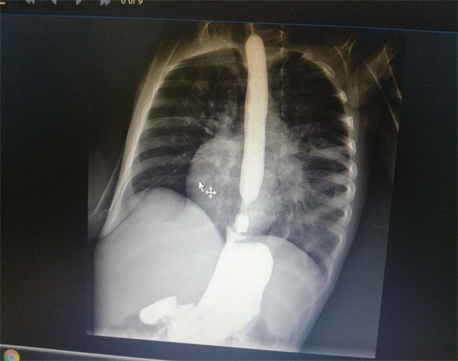

Medical records of 11 patients who underwent total esophagogastric separation (TEGS) with Roux en Y anastomosis for recurrent GERD in our institute in pediatric surgery unit, Medina children hospital, KSA during the period between Feb. 2011 to March 2018 were reviewed retrospectively. Selective criteria included all cases of recurrent GERD in NIC after fundoplications. TEGS was not performed in any case as a primary procedure. Their ages range between 6 - 14 years. Seven cases did TEGS for recurrent GERD symptoms after three fundoplications in three cases and two fundoplications in four cases. The recurrence of GERD was assessed clinically and radiologically. Clinical assessment was done by following cases of previous fundoplications as regarding improvement of body weight, signs of malnutrition, feeding tube problems, in addition to recurrent attacks of respiratory tract infections. Upper gastro-intestinal contrast studies were carried out to diagnose cases of recurrent reflux and give an idea about wrap strength (Figure 1 and Figure 2). Milk scan was needed for confirmation of GERD induced respiratory problems.

Figure 1. Severe GERD with hiatus hernia.